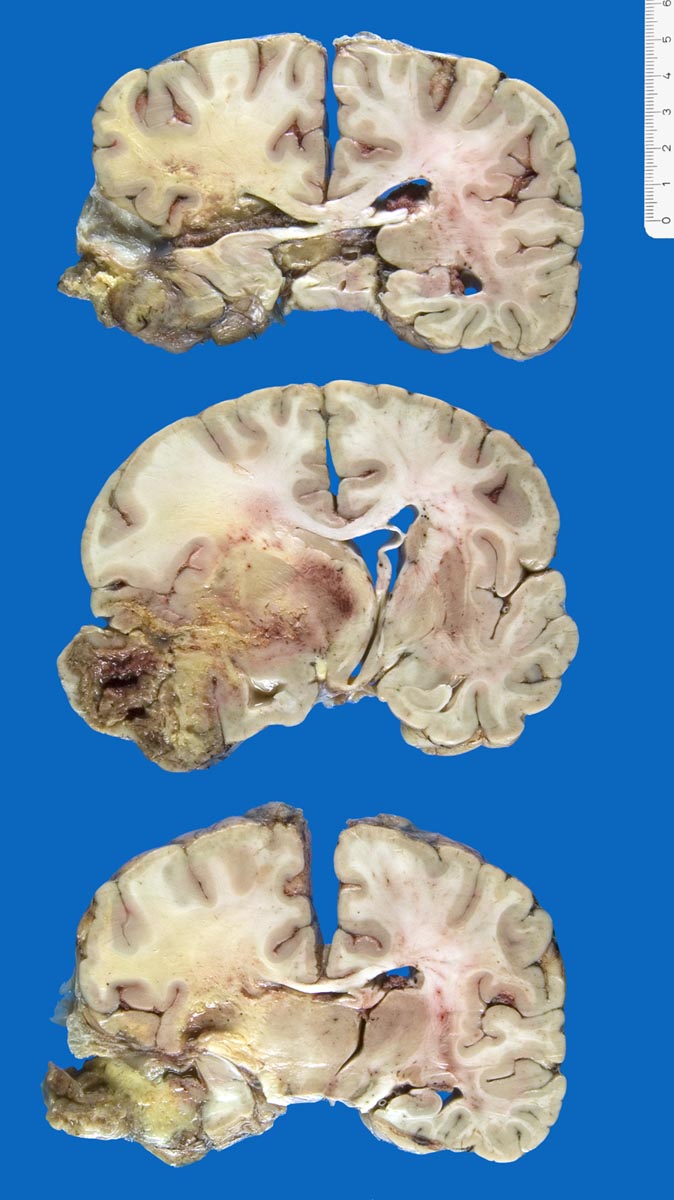

Die Schnittfläche ist auffallend bunt. Dies ist bedingt durch ein Nebeneinander von graurotem vitalem Tumorgewebe, gelben Nekrosen, roten Einblutungen und gelegentlich grünlichen Gallertzysten.

• Zellreicher Tumor mit sehr unscharfer Begrenzung zum normalen Hirnparenchym (rechts unten).

• Typische streifenförmige Nekrosen mit randständiger Palisadierung der Tumorzellen.

• Im Zentrum der Nekrose thrombosierte Gefässe umgeben von einem Saum vitaler Tumorzellen.

• Pathologische glomerulumartige zellreiche Gefässknäuel.

• Ausgeprägte Zellpolymorphie und Atypie.

• Mitosen.